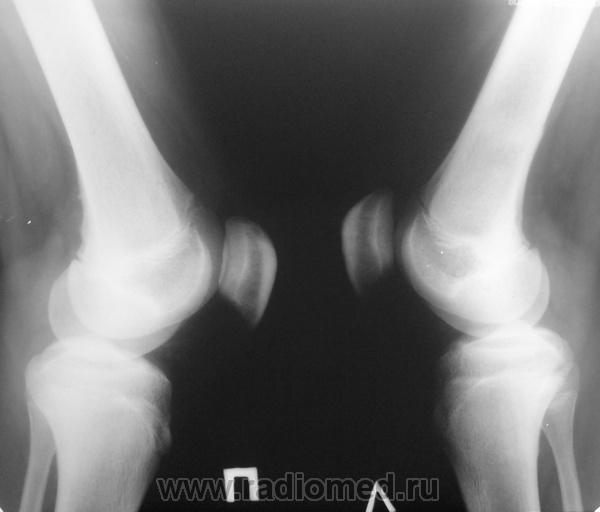

Мальчик 15 лет. Несколько месяцев назад начали беспокоить боли в коленных суставах. Травмы не было. Ребёнку был выставлен диагноз: болезнь Шлаттера, назначено лечение. На фоне лечения отмечалось значительное усиление болей, боли локализовались в левом коленном суставе. При дообследовании выявлена следующая рентгенологическая картина. Наши рентгенологи настаивают на срастающемся переломе. Но: 1) перелом без травмы? 2) бедро так не ломается

Линейный периостит, уже должен был рентгенологов насторожить.

Локальный гиперостоз, выраженный болевой синдром, структура губчатого вещества диафиза не изменена наводит только на остеойд-остеому.

Я бы на первое место поставила патологическую перестройку, так называемый, стрессовый перелом. Мальчик чем-нибудь занимается?

Согласна с Ola-la - рентгенологическая картина более всего соответствует стрессорному перелому, хотя для него характерна локализация в б/берцовой кости. Меня однако, смущает и настораживает клиника - это как раз тот случай, когда я бы не дала 100% гарантии, что так не может манифестировать остеосаркома... Поскольку другие методы (МРТ, сцинтиграфия) вряд ли помогут, я бы взяла пациента на короткое ( 2недели - месяц) динамическое наблюдение.

Да, на мой взгляд, состояние после обычного "травматического перелома" (трещина), не думаю, что имел место "патологический перелом", так как костная ткань "патологически изменена" минимально. "Перистальная реакция"локальная тоже есть, на КТ "локальная  зона склероза" - все это свидетельствует именно об этом. Хотя в памяти у меня хорошо отложился Ваш последний случай о локальном утолщении кортикального слоя, когда "яйца в гнезде" еще не было. То, что анамнестически "травмы не было" - ничего не значит. Вы, по всей видимости, тоже часто встречались с такими случаями, когда ребенок не акцентировал внимание на "травме", как таковой, хотя клиника есть, боль есть. Конечно, рентгенограммы - не дай бог - ни скиалогии, ни структуры.